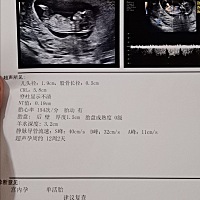

哈哈 晒晒我的孕照